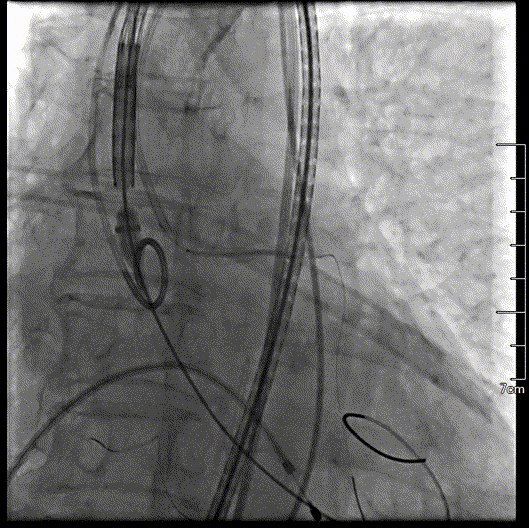

瓣膜初始定位